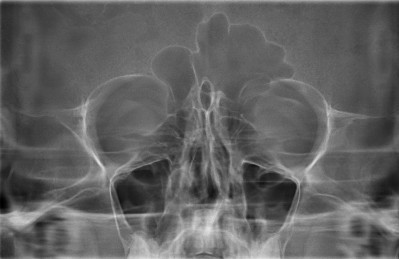

Кроме того выполняется рентгенологическое исследование – рентген придаточных носовых пазух.

При этом в полостях практически всегда определяется уровень жидкости. Для подтверждения диагноза также можно выполнить компьютерную томографию. Однако это довольно дорогостоящий метод, который не всегда дает больше информации, чем рентген.

По этой причине компьютерную томографию не назначают всем пациентам. Этот метод используют лишь в тех случаях, когда рентгенологическое исследование является малоинформативным. Важной является диагностическая пункция носовых пазух, которая позволяет определить наличие гноя в полости.